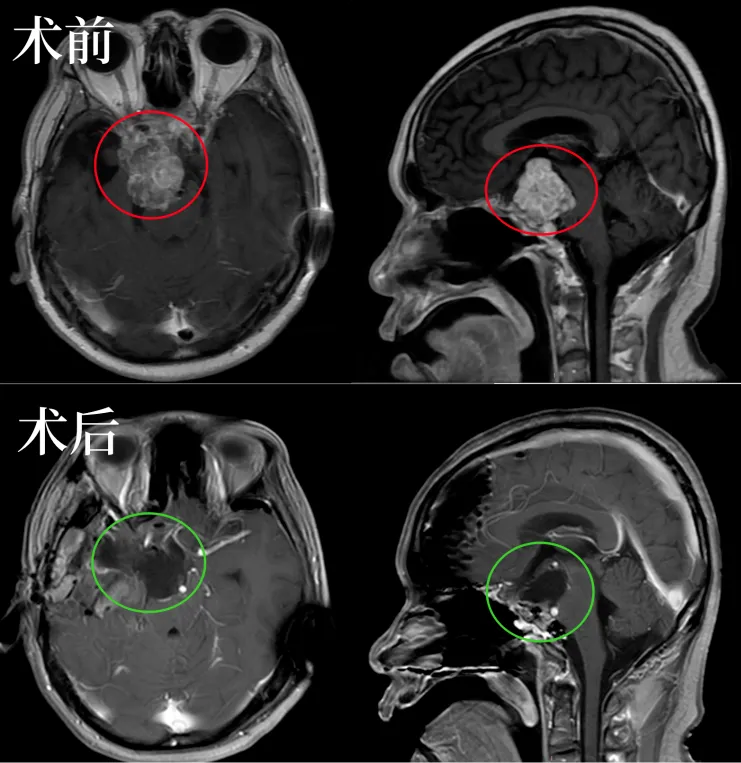

福洛里希教授案例解析 国际神经外科联合会(WFNS) 颅底手术委员会前主席, 发表了筷子技术神经内镜联合显微镜双镜联合 全切颅颈交界区较大脊索瘤手术研究成果。 其中一例国际疑...